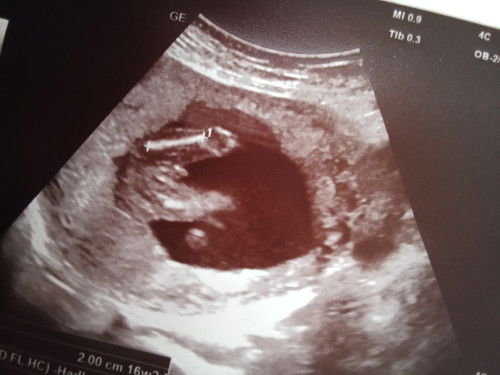

การอัลตราซาวด์

ครั้งแรก14วิค วันนี้มีนัด 16วิคเพิ่งซาวมาเลยค่ะ ปกติจะซาวตอน16กับช่วงใกล้คลอดค่ะ แต่ท้องโตกว่าอายุครรภ์หมอเลยซาวดูอายุครรภ์ตอน14วิคค่ะ